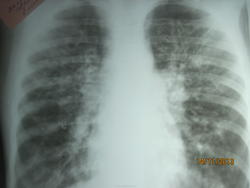

В легких с 2х сторон определяется усиление, деформация и ячеистость легочного рисунка. Корни инфильтрированы, расширены. синусы срезаны. Границы сердца в пределах восрастной нормы. З-е: Муковисцидоз. Правильно?

Ребенку сейчас 6лет, с 2х мес на учете с диагнозом Муковисцидоз, смешанная форма. КТ от 24.09.13г ( попало описание ко мне в руки чисто случайно, снимков при себе нет) Легочная ткань прозрачна, пневматизация неравномерноя-участки гиповентиляции чередуются с участками эмфизематозного вздутия. Без динамики, сохраняются бронхоэктазы в проекции нижних долей, прежних размеров.Бронхо-сосудистый рисунок диффузно усилен за счет интерстициального компонента, деформироан по "сетчатому" типу. Бронхи в проекции верхних долей сближены, расширены, стенки их утолщены, в проекции S1,2 справа-бронхоэктазы,d до 4мм, содержащие секрет. определяются цилиндрические бронхоэктазы нижних отделов обоих легких до 4-5-7 мм в диаметре, слева содержат секрет. В S6 слева бронхоэктазы до 7мм в диаметре, склонные к слиянию, содержат высоколотостной секрет. Просвет трахеи, главных бронхов не изменен. Корни структурны, расширены. Синусы плевры свободны. Тень сердца не изменена. Куполы диафрагмы расположены обычно. Заключение: КТ картина муковисцидоза. Бронхоэктазы. КТ картина без динамики.